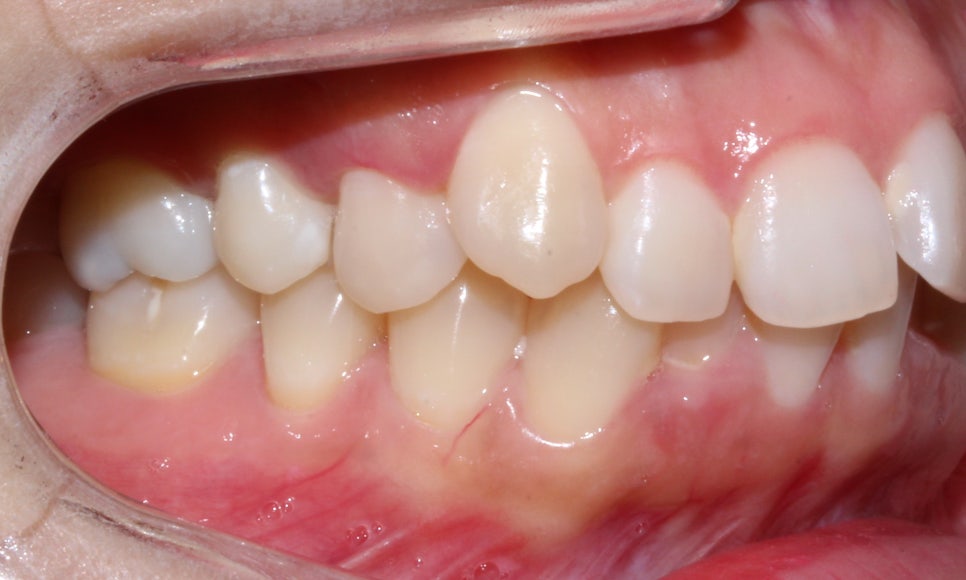

돌출입, 덧니교정 후 사진

돌출입, 덧니치아 2D교정으로 완성! by.투디치과(2D치과)

<14개월 교정이 끝난 후 모습>

교정이 끝난 모습입니다:-D

총갱이 심했던 하악도 자연스럽게

교정이 잘 마쳐졌습니다.

이번 환자분의 경우처럼 덧니가

심할 경우에는 반드시 정밀한 진단과

상담을 통해 인접치 부근의

블랙트라이앵글 발생 가능성을

확인하는 것을 추천드리며

투디차과의 전문적인 심미보정

치료 과정을 통해

치아 사이의 블랙트라이앵글을

효과적으로 제거 할 수 있도록

계획을 세우는 것이 중요합니다.

예쁜 미소를 되찾으신 환자분!

이제 아름다운 미소를 맘껏 뽐내시기 바라요~~